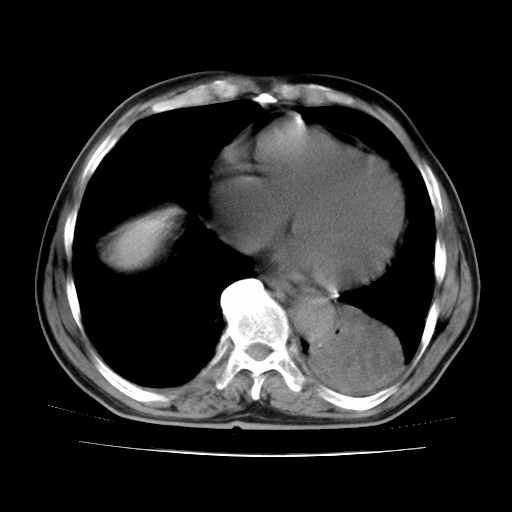

男,71岁,咳嗽,气喘10年,再发并咯血.胸片见气胸

考虑  左肺中心型肺癌伴阻塞性肺炎,肺不张,纵膈淋巴结肿大。慢支炎,肺气肿,左侧气胸肺压缩5%

左侧中央型肺癌伴纵膈淋巴结转移。

左肺中心型肺癌伴阻塞性肺炎,肺不张,纵膈淋巴结肿大

1)考虑左肺中心型肺癌伴阻塞性肺炎、左肺下叶肺不张、左侧肺气肿,纵膈淋巴结转移。2)左侧气胸(肺组织压缩约5%)。

左肺中心型肺癌伴阻塞性肺不张、肺气肿 。

1)考虑左肺中心型肺癌伴阻塞性肺炎、左肺下叶肺不张、左侧肺气肿,纵膈淋巴结转移。2)左侧气胸。